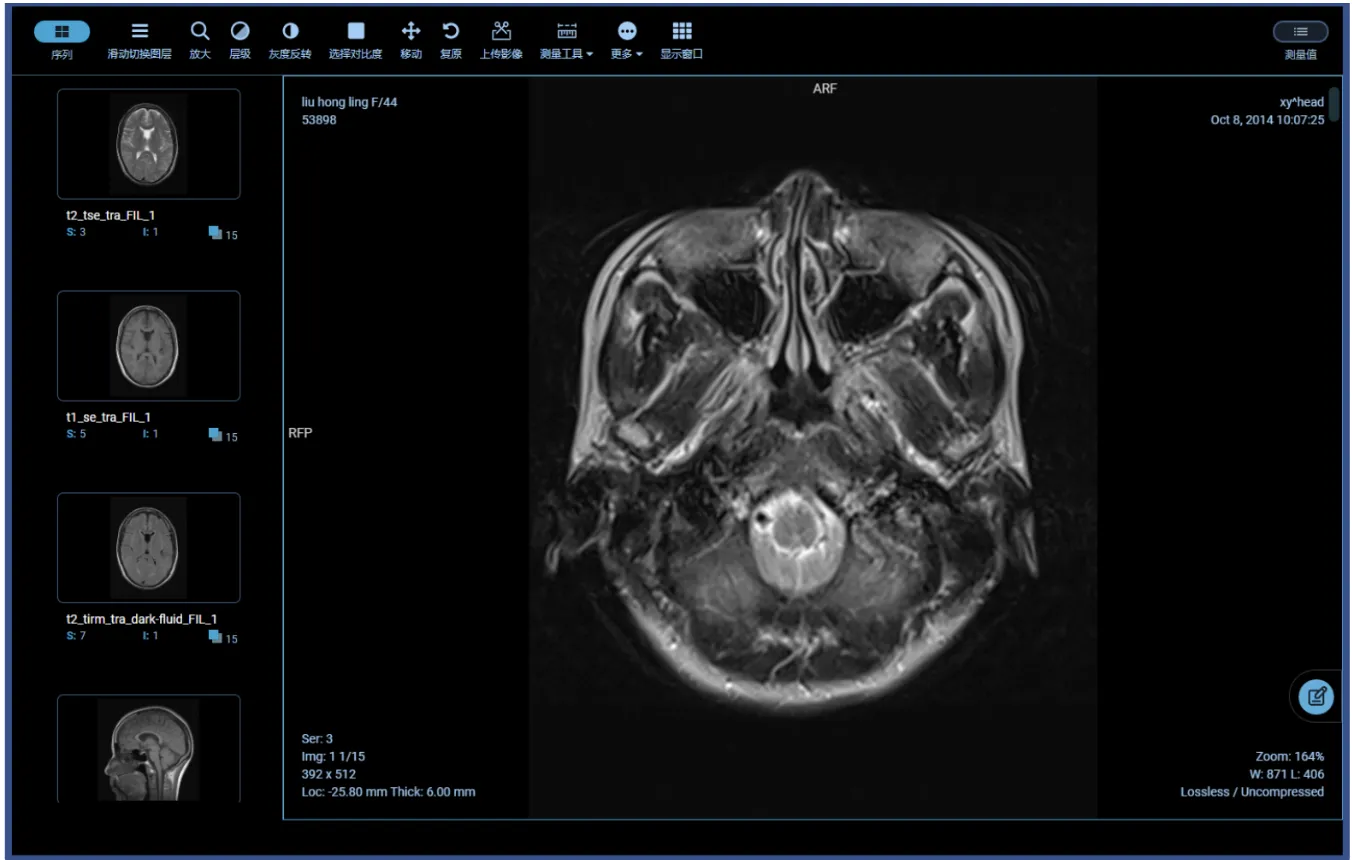

- 🩻 核心PACS阅片引擎 (Web Viewer)

极速加载引擎: 采用按需加载与无损压缩传输技术,即使在普通宽带下也能实现大序列CT图像的“边下边看”。

专业影像处理工具包:

基础操作: 无级缩放、漫游、旋转、翻转、放大镜。

专业调节: 自定义窗宽窗位(支持预设腹部、骨骼、肺部等模式)、伪彩渲染。

精准测量: 长度、角度、面积、CT值(HU值)测量、心胸比自动计算。

🌟 高级三维重建 (硬核卖点): 纯前端实现 MPR (多平面重建)、CPR (曲面重建)、MIP (最大密度投影)、VR (容积渲染),媲美传统工作站的渲染效果。

影像对比与序列协同: 支持多屏多序列同步滚动阅片,方便随访复查对比。